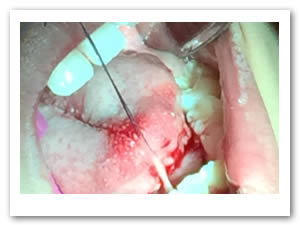

• Se realizó una incisión horizontal en la parte media del frenillo con hoja de bisturí No. 15 y mango No. 3, posteriormente se comenzó a cortar el frenillo de arriba abajo cuidando la anatomía de la región y la zona de las carúnculas sublinguales de los conductos de Wharton y Rivini. (Figuras 5 y 6).

Figuras 5 y 6. Incisión y corte del frenillo.

• Se eliminó el frenillo en su totalidad  con la ayuda de tijeras iris recta y hoja de bisturí del No. 15 así como todo el tejido residual fibroso correspondiente al frenillo. Se realizó genioplastia con pinza de mosco y disección roma para liberar adecuadamente la inserción frénica hasta la cara lingual de los incisivos inferiores. (Figuras  7, 8 y 9)

Figuras 7 y 8. Eliminación total del frenillo y genioplastia